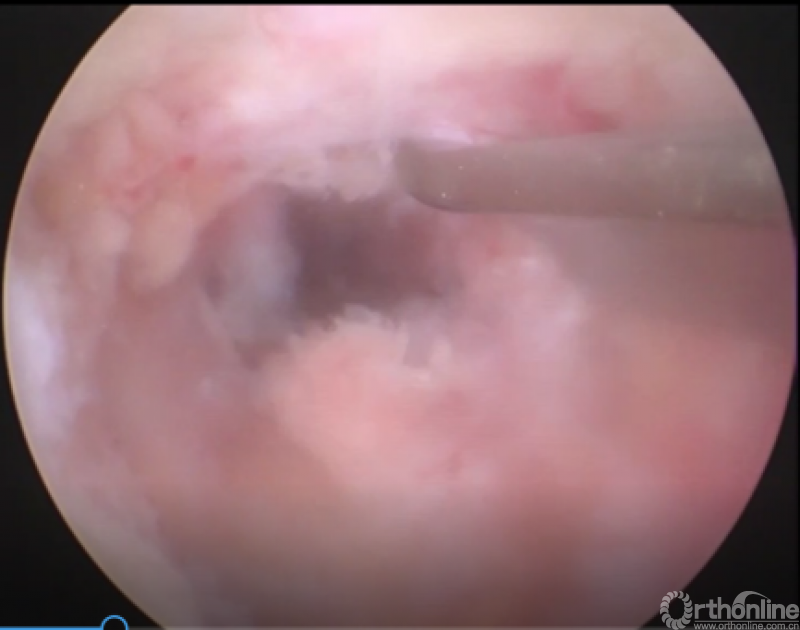

第二步“辨”:镜下辨别下关节突关节囊;

第三步“凿”:凿除部分下关节突,显露上关节突及黄韧带;

第四步“分”:分离上关节突及黄韧带;

第五步“咬”:咬除部分上关节突,显露椎间盘及神经根;

第六步“切”:切除椎间盘;

第七步“旋”:旋转舌形套管保护神经根;